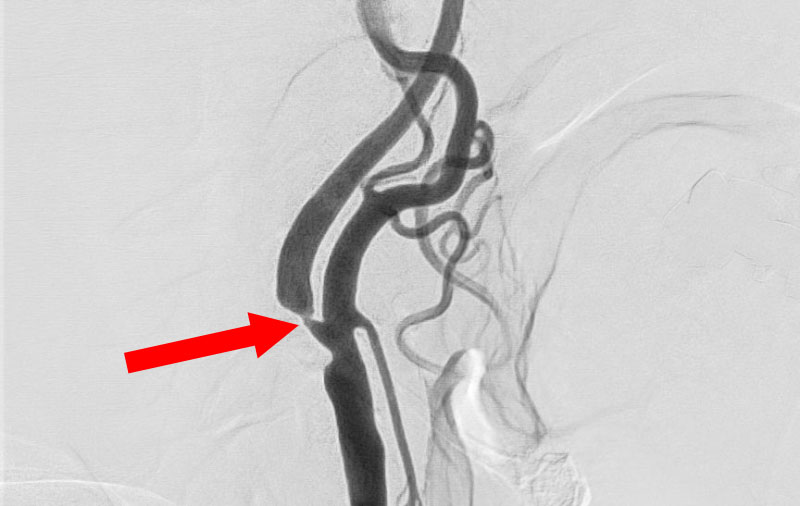

'25年10月

左総頚動脈狭窄症

30代

院内外来

No.1590 手術前

No.1590 手術中

No.1590 手術後